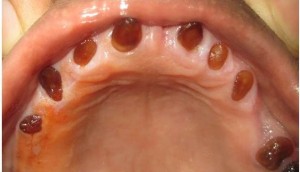

Несовершенный дентиногенез. Наследственное нарушение образования зубных тканей мезенхимного происхождения. Эта патология нередко сочетается с системным или очаговым несовершенным остеогенезом. Преимущественно поражаются все зубы. Исключение составляют поздние формы несовершенного остеогенеза. Зубы окрашены в желтый, коричневый и почти черный цвет. Поверхность их гладкая, прозрачная, легко поддается обработке режущими инструментами. Одновременно поражается пульпа.

Клиническая картина. Структура эмали не изменена, но из-за несовершенства дентина его соединение с эмалью непрочное, приводящее к отколу эмали. В запущенных случаях трудно различить пороки эмали и дентина. Ведущим дифференциально-диагностическим признаком является отсутствие в зубах с несовершенным амелогенезом изменений в форме и величине корней. У детей с несовершенным дентиногенезом корни имеют пороки развития, истончены, укорочены, полость пульпы может быть деформирована.